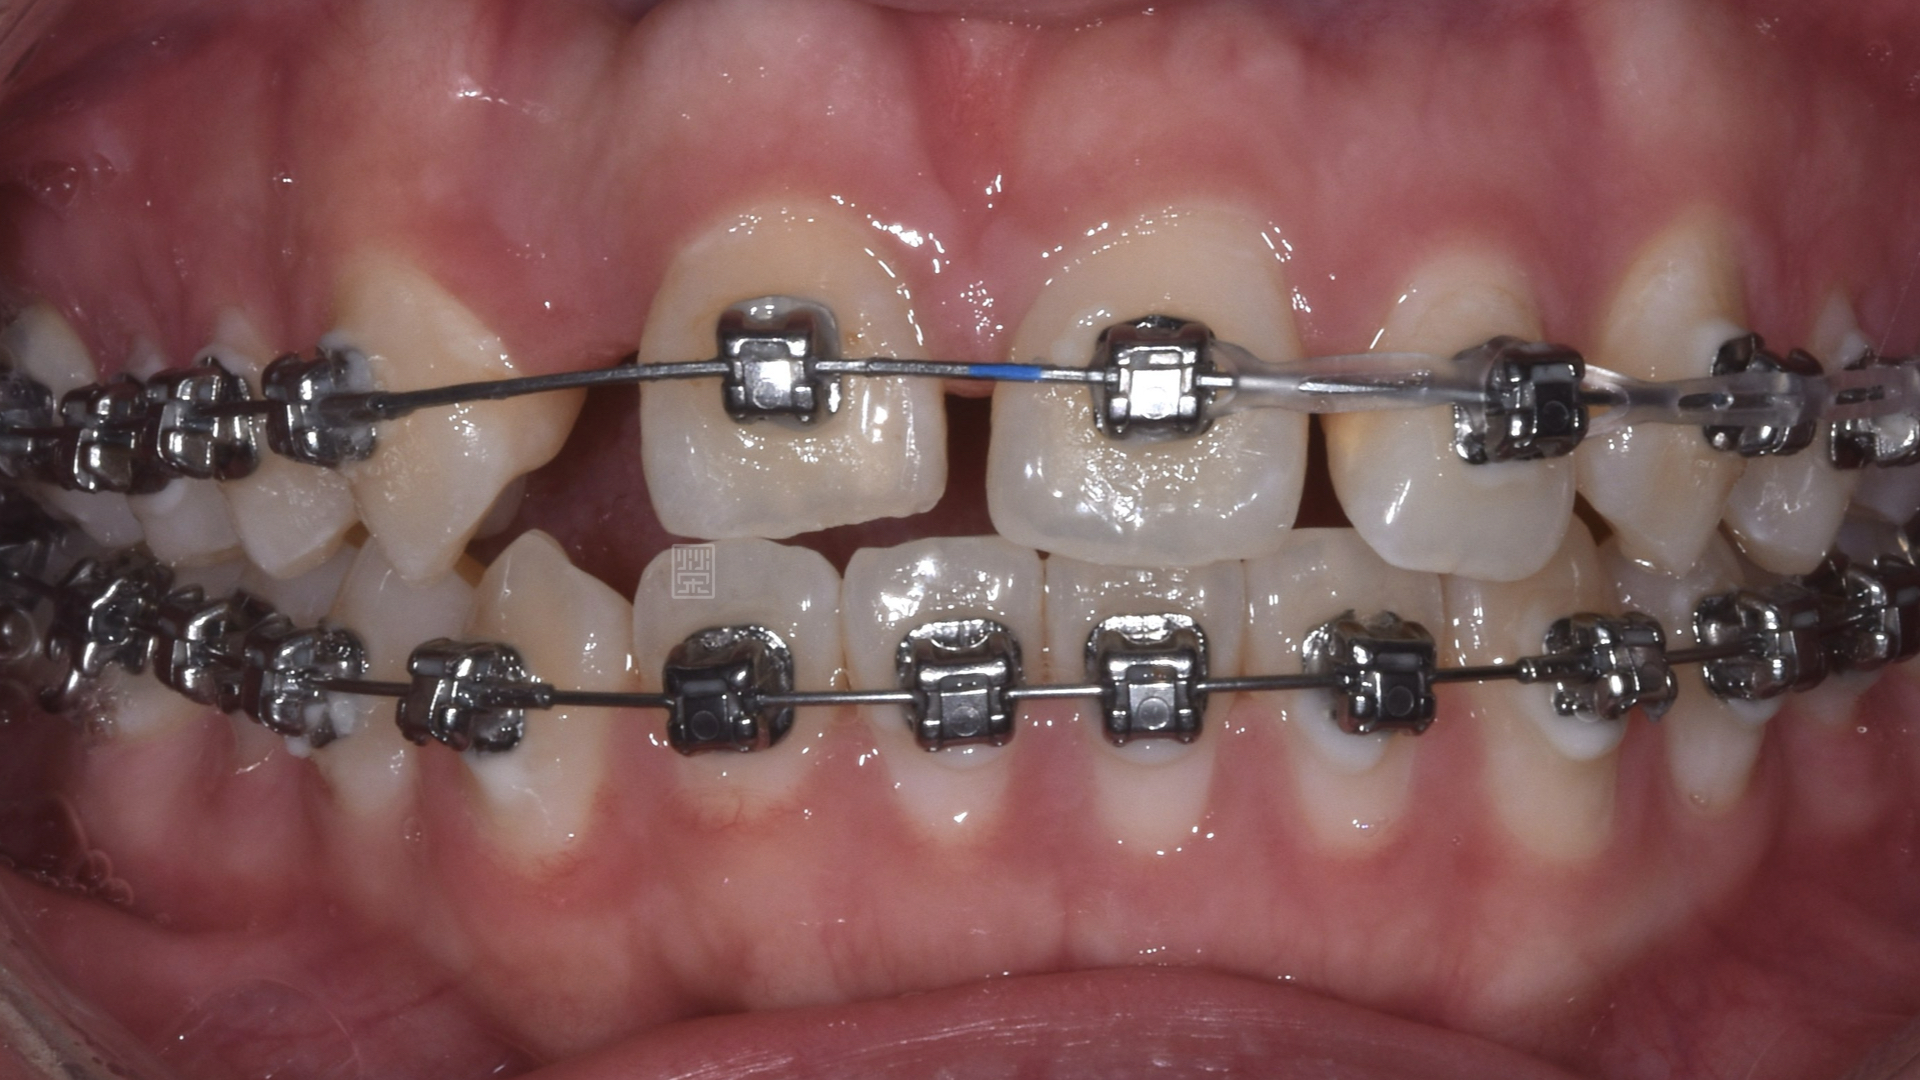

矯正移出側門牙空間

皮質骨切開手術增加牙齒移動

矯正時因牙齒沾黏骨頭無法移動